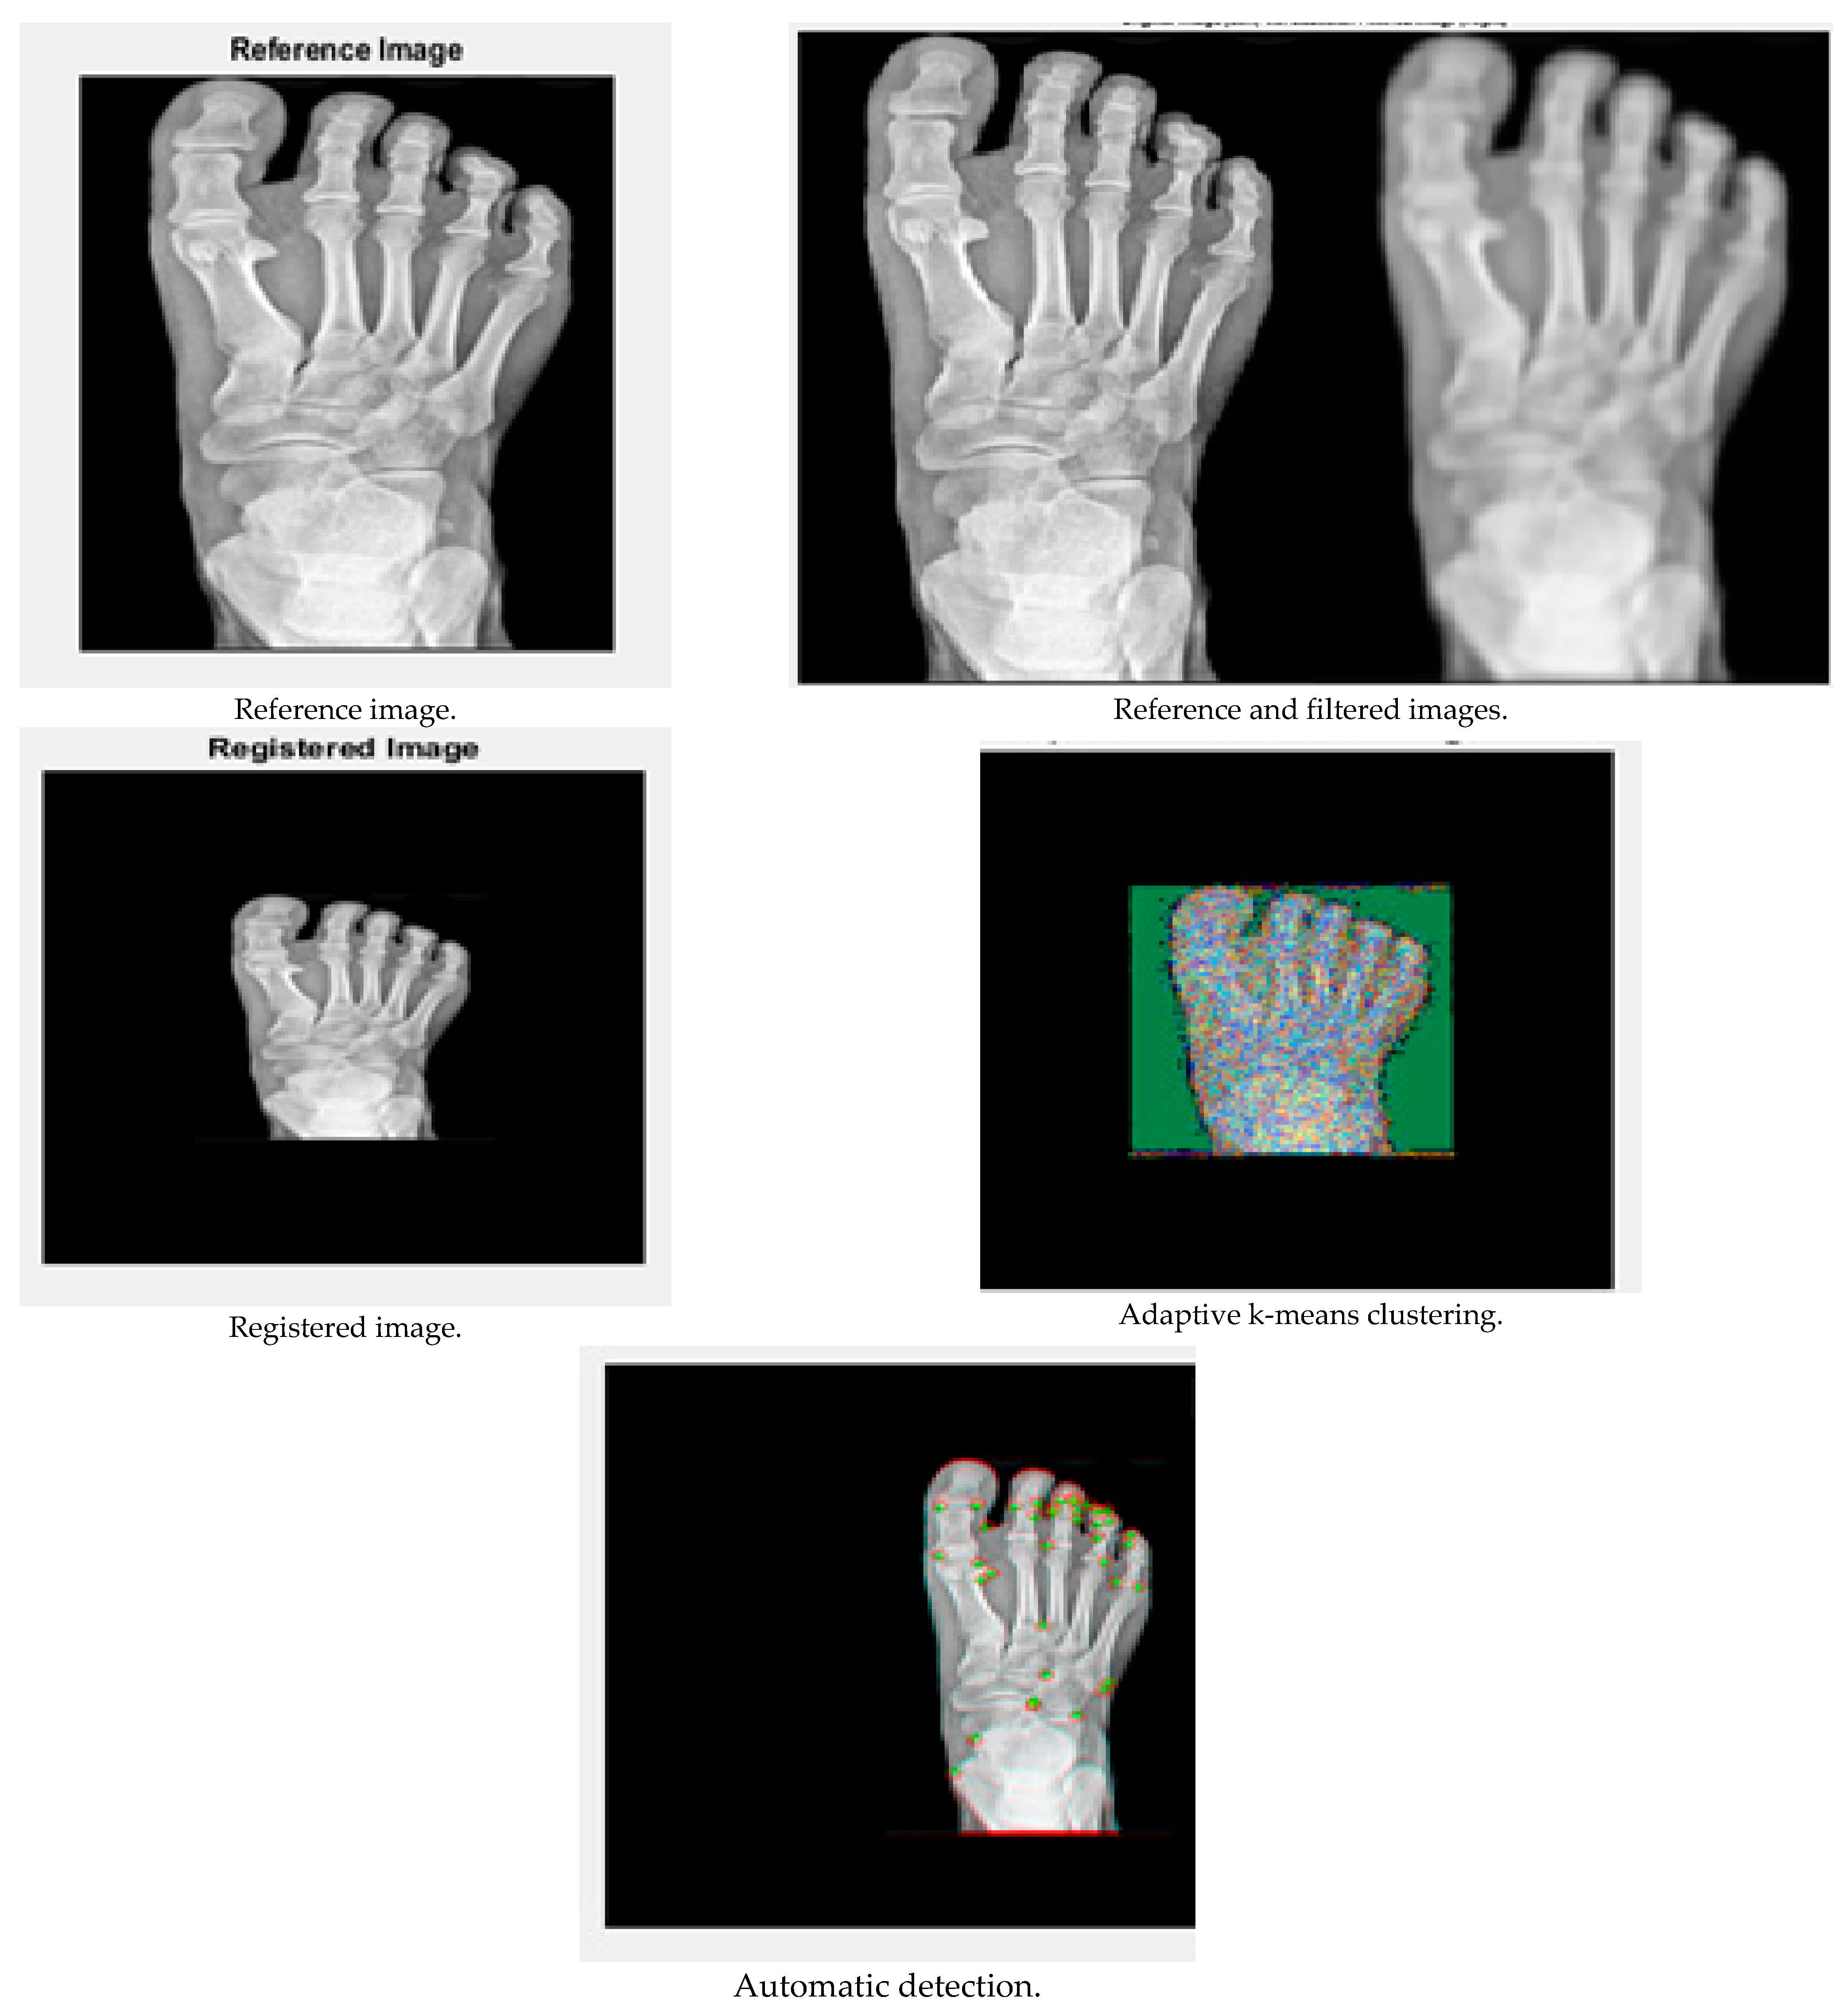

The performance of the results is demonstrated in this Results and Discussion section. The input X-ray images were taken from the website kaggle, and the results were obtained using MATLAB R2019a. The results are shown in Figure 3 and Figure 4:

Figure 4.

Performance analysis of image 2.